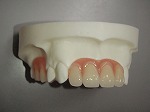

◆総入れ歯

当院の総入れ歯では、リンガライズド・オクルージョンという特別な噛み合わせで製作しております。この噛み合わせの特徴は、小さな力で食品を破砕することが可能となり、ハグキが吸収して食事中、入れ歯の安定が悪い方にお勧めです。